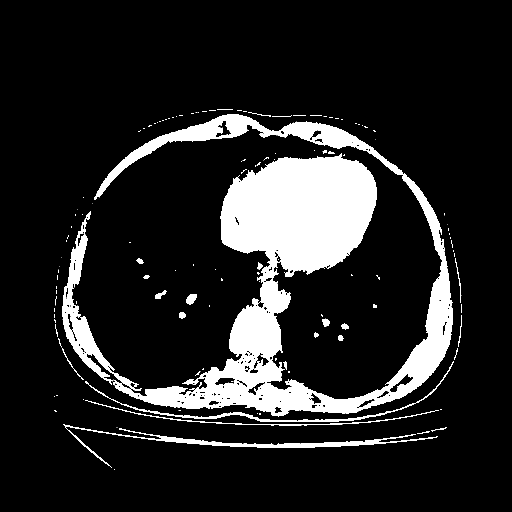

Reconstructed NATIVE CT scan (cycle consistency)

Full window (WL 1023.5, WW 4095 β†’ Low βˆ’1024, High +3071)

Actual HU range: [-1024.0, 3071.0]